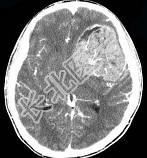

- 单项选择题男,15岁, 进行性头痛1年余,CT检查如图所示, 最可能的诊断是 ( )